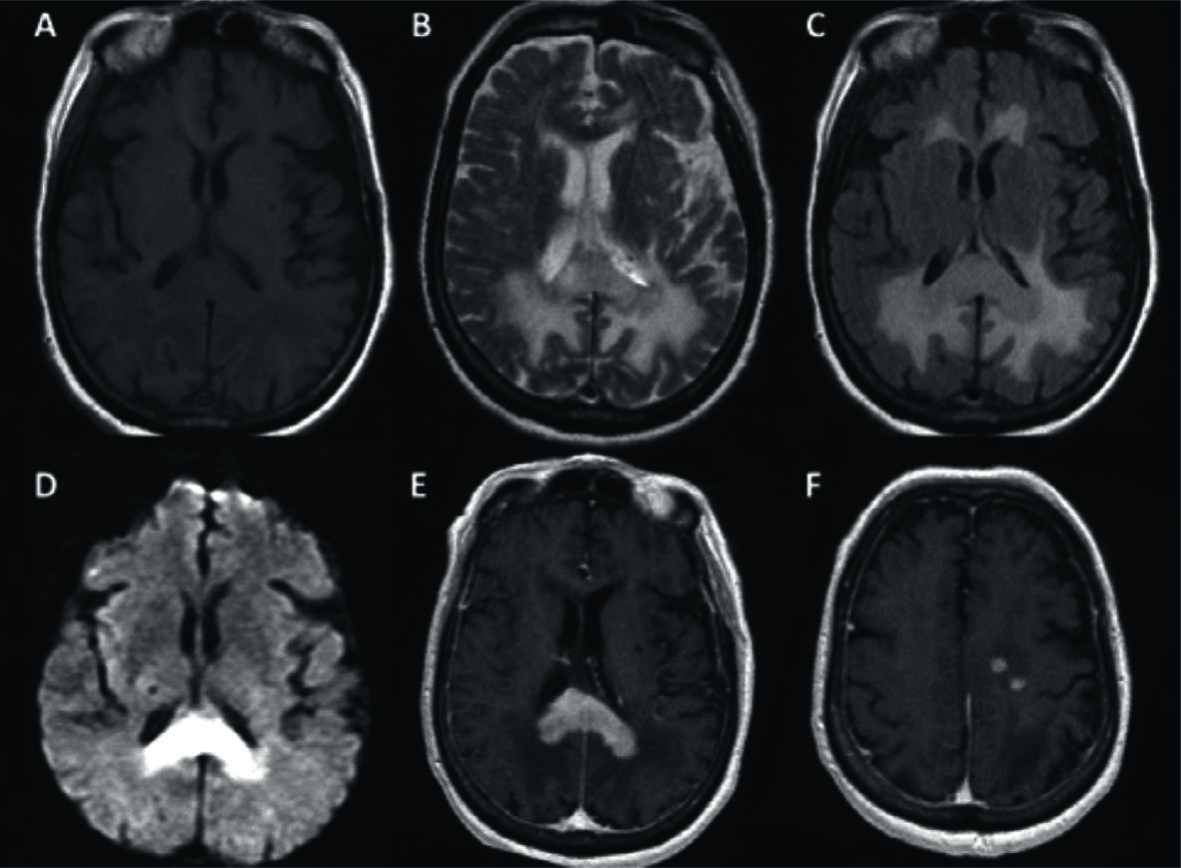

Figura 1

LPSN multifocal con compromiso del cuerpo calloso.

Paciente con diagnóstico de LPSN con múltiples focos de realce, el principal en el CC, sector posterior. Se observa el comportamiento más frecuente: hipointensidad en T1 (A), hipointensa en T2 con respecto a la SG cerebral (B), con edema asociado en FLAIR (C) y restricción en difusión (D). Con el medio de contraste se observa el intenso y homogéneo realce con bordes irregulares (E) y al menos 2 focos adicionales en la sustancia blanca subcortical del lado izquierdo (F).